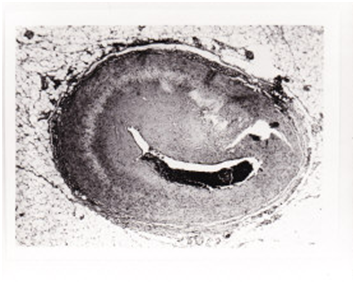

2 pts (4.3%) Table 2 showed sudden H as a symptom of impending rupture (respectively from 118/86 mmHg to 180/95 mmHg and 145/90 mmHg to 190/98 mmHg) and chest pain resistant to opiates. They deceased within 1 hour from increased H. The other 44 pts with PCR were hypertensive in 27 cases (61%) at the admission, while 17 (39%) displayed no H. Pts with rupture (Figures 1-4), and (Table 3) had a statistically significant number of multiple coronary alterations, cardiac hypertrophy (mean heart weight 627+/-188 grams and left ventricle wall thickness 25+/-3 mm vs 400+/-75 grams for heart weight and 14+/-2mm for left ventricle wall thickness in pts with no rupture), irregular areas of confluent fibrosis and coronary narrowing up to 90% with a high incidence of occlusive thrombi.

Figure 4 Severe stenosis of the left coronary descending artery in PCR.